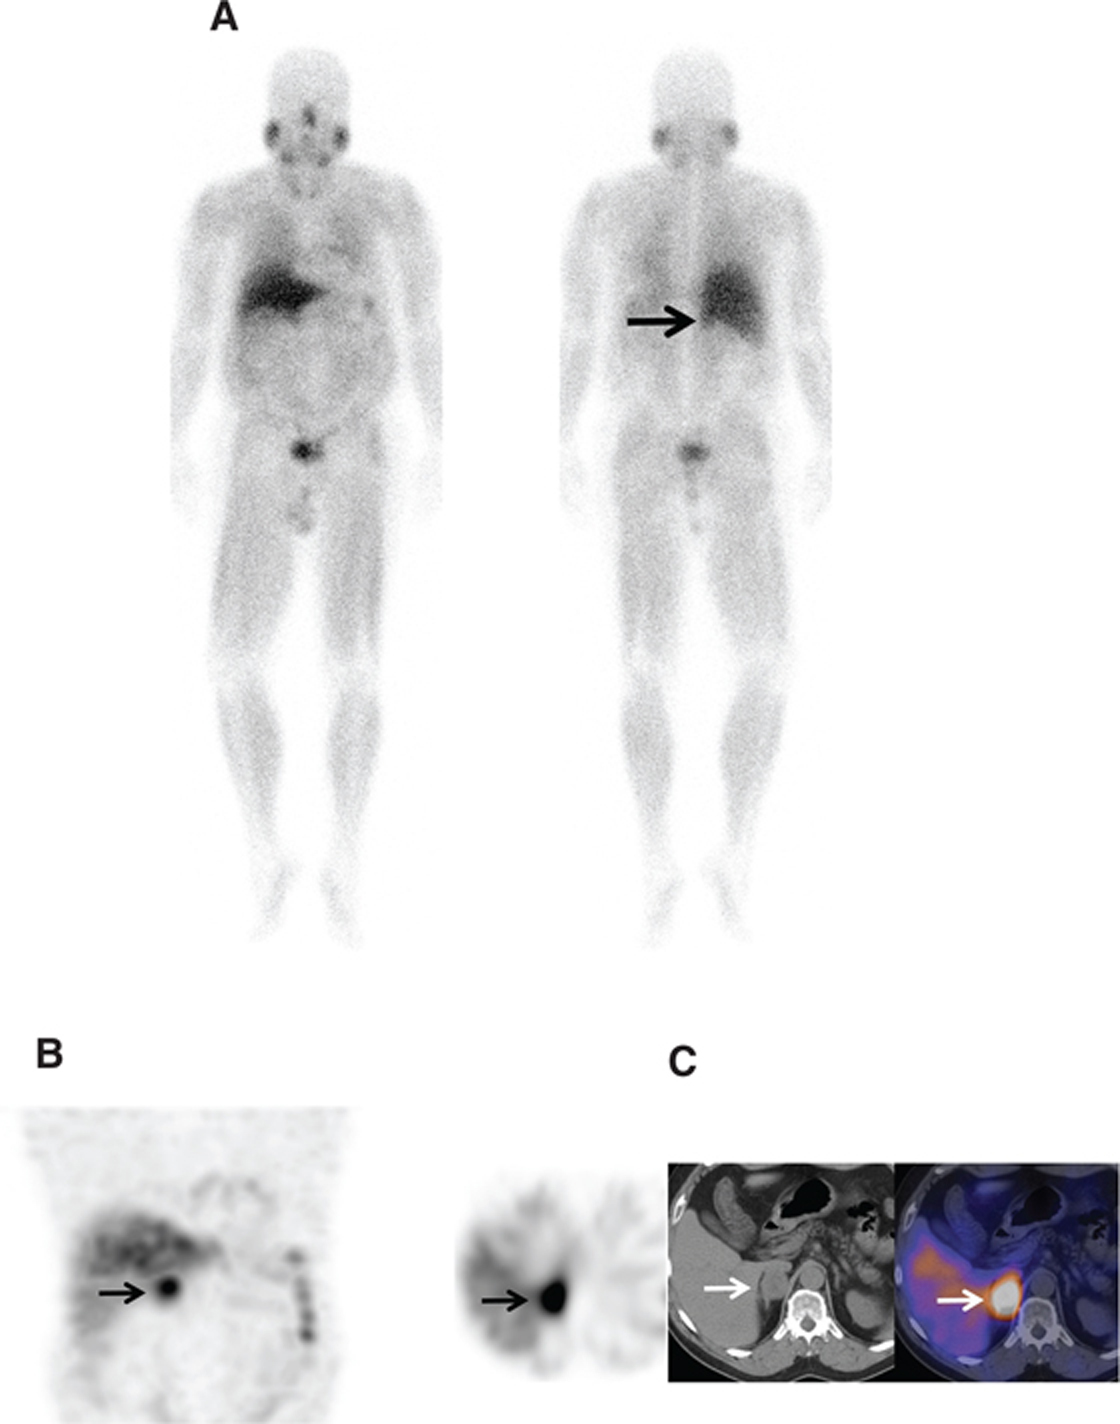

Ga-68 DOTATATE, with affinity to SSTR 2 and 5, was approved for use by the FDA in June 2016 (NETSPOT®).68 Ga-DOTATATE is indicated for localization of SSTR-positive NETs in both adults and children. Typical normal biodistribution is uptake in the pituitary, thyroid, adrenals, liver, spleen, uncinate process of pancreas, kidneys, and bladder. The method of evaluation is similar to octreoscan. Focal increased activity, not typical of normal distribution, is suspicious for disease (Figures 8 and 9). Similar to In-111 pentetreotide, false-positive findings can be seen and misinterpreted, and it is important to be aware of normal distribution and variants. No set diagnostic criteria currently exist for DOTATATE imaging, although there has been a proposal to standardize the reporting criteria using a 5-point structured system (54).

Fig 9

Figure 9 A 55-year-old woman with metastatic paraganglioma having an initial Ki67 proliferation index of 25% and strong SSTR2A immunostain but without SDHB mutation on germline testing. (A) Ga-68 DOTATATE PET/CT maximum intensity projection (MIP) images of the skull vertex to the proximal thigh on the left show widespread somatostatin receptor-positive metastatic disease, with progressive disease on the right image with enlarging pelvic osseous lesions (arrows). (B) Ga-68 DOTATATE PET/CT axial fused PET/CT, axial PET, and sagittal fused PET/CT images show enlarging vertebral lesion (arrows) on the current study (top images) as compared to the prior (bottom images).